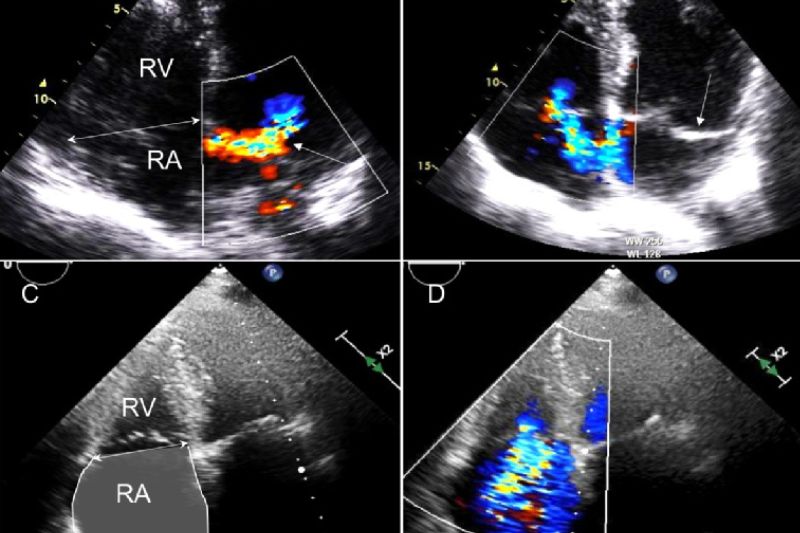

Các phương pháp cận lâm sàng như điện tâm đồ, siêu âm Doppler, chụp X-quang, chụp MRI,… cung cấp nhiều thông tin quan trọng và cần thiết để bác sĩ đưa ra kết luận cuối cùng.